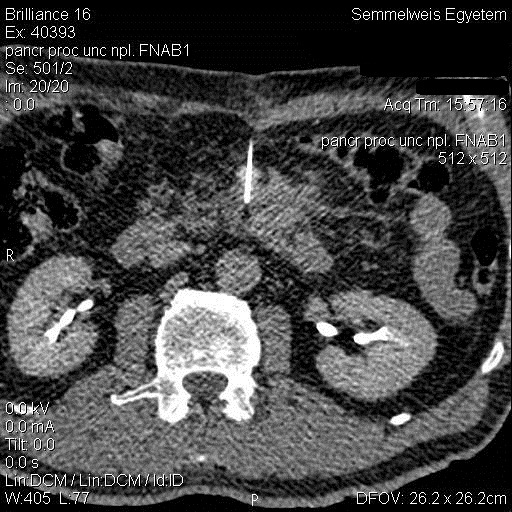

19.2.2.2. CT guided biopsy

Ideal method if the lesion is located either in the chest (figure 5.), mediastinum, retroperitoneum (figure 6.) or the pelvis.

Image

Figure 6. – CT guided pancreatic biopsy